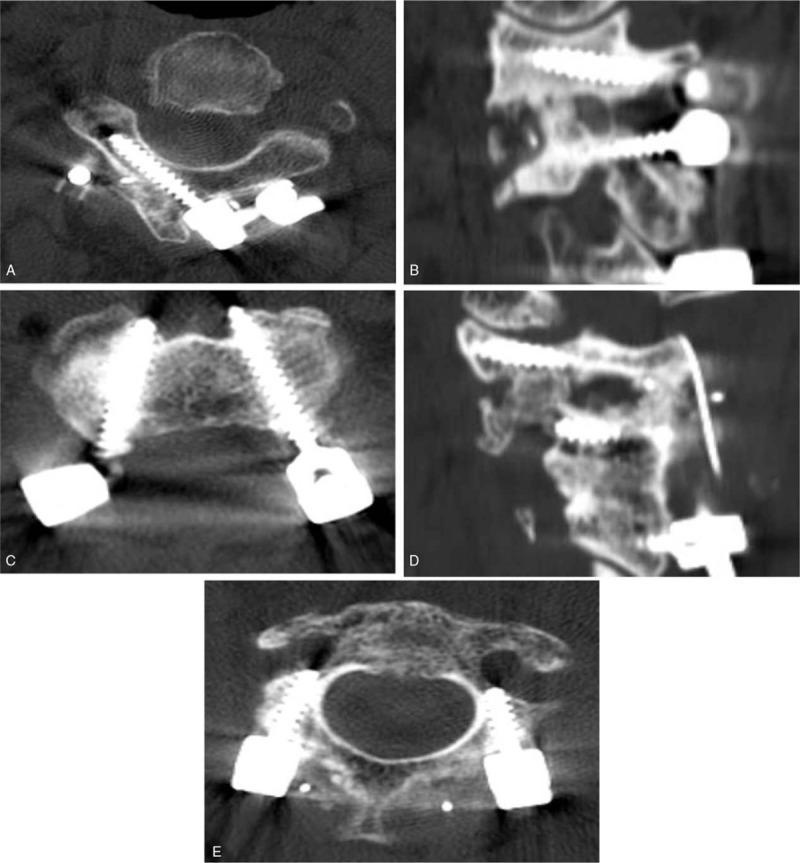

An observational study.To evaluate the safeties of placing three different alternative C2 screws using the freehand technique under high riding vertebral artery (HRVA) and to analyze the C2 morphometry in patients with HRVA.A retrospective analysis of radiologic data was performed on patients that underwent C2 instrumentation from September 2004 to December 2017. Two hundred fifty-one patients were included, and 90 of these patients (35.9%) had a unilateral or bilateral HRVA. We placed three alternative C2 screws including superior pars, inferior pars, and translaminar screws. Computed tomography was used to assess cortical breeches of screw placement and obtain morphometric measurements of C2 pars and lamina, that is, superior pars height/length, inferior pars length, and laminar thickness/length. We used the modification of the all India Institute of Medical Sciences outcome to define cortical breach.In total, 117 alternative C2 screws were inserted in 90 patients; 7 superior pars screws (6%), 69 inferior pars screws (59.0%), and 41 translaminar (35%) screws. Although cortical breaches occurred during 31 screw placements (26.5%), these were unacceptable in only two cases (1.7%). No symptomatic neurovascular complication was observed after screw placement in any case. Mean height of C2 superior pars was 3.8 ± 1.8 mm and mean thickness of C2 lamina was 5.2 ± 1.1 mm. Mean lengths of superior pars, inferior pars, and lamina were 17.8 ± 3.0 mm, 13.6 ± 2.2 mm, and 26.7 ± 3.3 mm, respectively. Superior pars height and lamina thickness < 3.5 mm that was a minimal diameter of cervical screw were 49.6% and 6.8%, alternative C2 screw was not available in these cases.Placements of alternative C2 screws using the freehand technique were achieved accurately and safely in patients with HRVA. However, preoperative morphometric evaluation is essential to determine the best option for C2 instrumentation and C2 screw length to avoid neurovascular complications.

一项观察性研究。旨在评估在高位椎动脉(HRVA)情况下徒手置入三种不同替代C2螺钉的安全性,并分析HRVA患者的C2形态学。对2004年9月至2017年12月期间接受C2器械植入的患者的放射学数据进行回顾性分析。共纳入251例患者,其中90例(35.9%)有单侧或双侧HRVA。我们置入了三种替代C2螺钉,包括上关节突螺钉、下关节突螺钉和椎板螺钉。使用计算机断层扫描评估螺钉置入的皮质骨穿透情况,并获取C2关节突和椎板的形态学测量值,即上关节突高度/长度、下关节突长度和椎板厚度/长度。我们采用全印度医学科学研究所结果的改良版来定义皮质骨穿透。

总共在90例患者中置入了117枚替代C2螺钉;7枚上关节突螺钉(6%)、69枚下关节突螺钉(59.0%)和41枚椎板螺钉(35%)。尽管在31次螺钉置入过程中发生了皮质骨穿透(26.5%),但只有2例(1.7%)是不可接受的。在任何情况下,螺钉置入后均未观察到有症状的神经血管并发症。C2上关节突的平均高度为3.8±1.8mm,C2椎板的平均厚度为5.2±1.1mm。上关节突、下关节突和椎板的平均长度分别为17.8±3.0mm、13.6±2.2mm和26.7±3.3mm。上关节突高度和椎板厚度<3.5mm(这是颈椎螺钉的最小直径)的情况分别为49.6%和6.8%,在这些情况下无法使用替代C2螺钉。